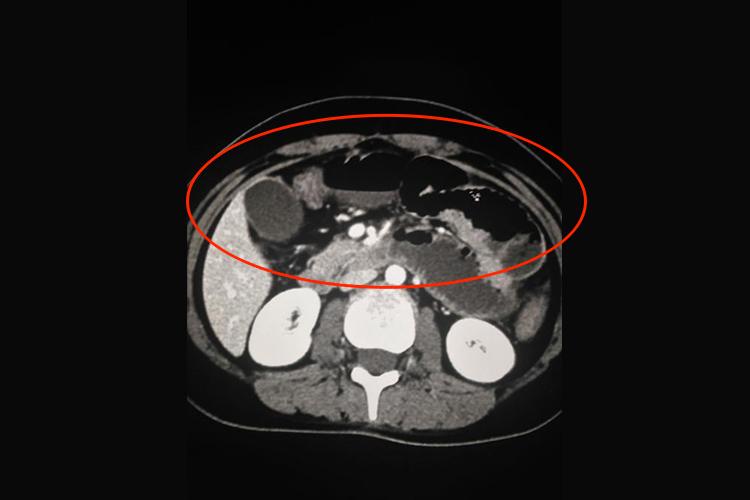

CT:肠梗阻患者进行CT检查,会显示扩张的肠曲,并可见多个肠腔内气-液平面。如果肠管互相融合成团,或与腹壁相连,提示为粘连性肠梗阻。如有肠套叠,则可显示出典型CT征象,出现三层肠壁征。